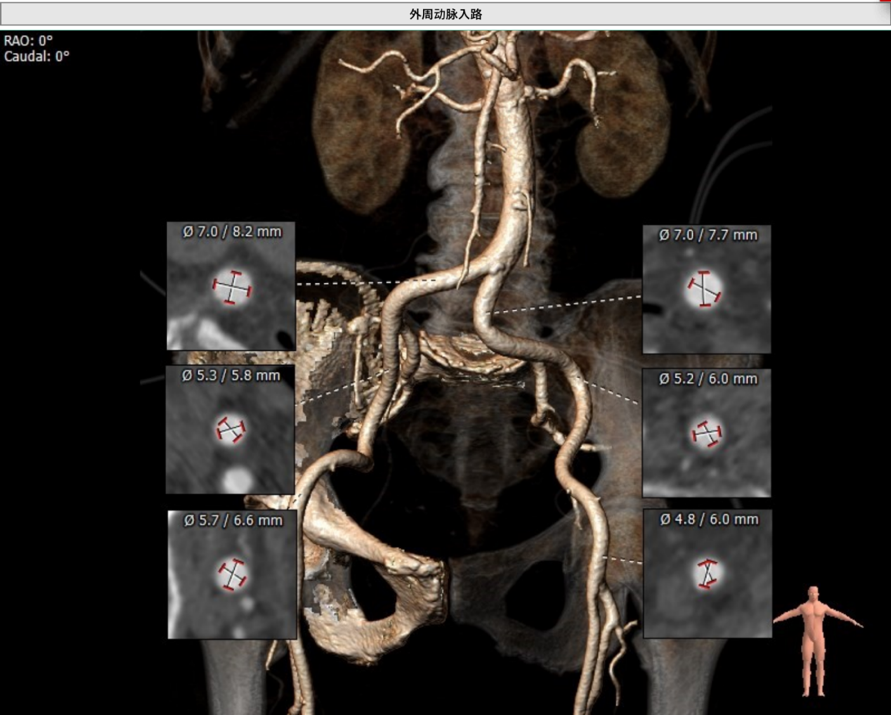

外周血管入路

外周血管入路轻微扭曲,直径合适